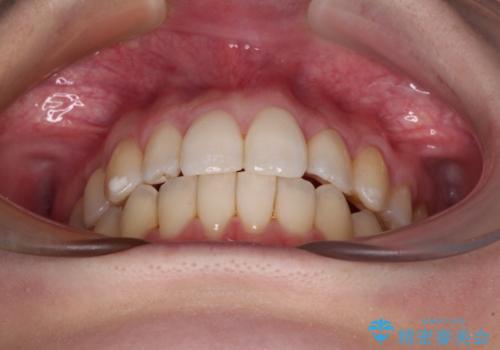

補助装置を併用したインビザラインでの八重歯の抜歯矯正

骨格的に下顎が右側に変位していたため、上下正中を合わせることは困難であることは分かっていました。それでも、なるべく合わせるようにとしたため、治療期間は長期間となりました。

長期間とはなりましたが、咬み合わせが改善され、患者様には大変満足していただきました。